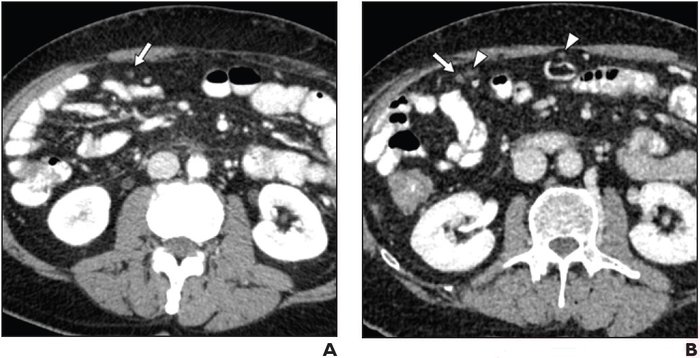

66-Year-Old Man With Locally Advanced Pancreatic Cancer Undergoing Chemotherapy: (A) Axial image from contrast-enhanced CT using positive oral contrast material, performed to monitor treatment response. Examination clinically interpreted as not showing metastatic disease. Unblinded retrospective image review shows tiny omental nodule (arrow) near bowel loops. Adequacy of bowel filling with contrast material rated very good. Both blinded retrospective readers detected nodule. (B) Axial image from contrast-enhanced CT performed two months later shows slight increase in size of nodule (arrow) and several new nodules (arrowheads), confirming lesion as missed malignant deposit. Image courtesy of American Roentgen Ray Society (ARRS), American Journal of Roentgenology (AJR)

April 27, 2022 — According to ARRS’ American Journal of Roentgenology (AJR), the selection of oral contrast agent and optimization of bowel preparation for oncologic computed tomography (CT) could help avoid potentially severe clinical consequences of missed malignant deposits.

“CT has suboptimal NPV for malignant deposits in intraabdominal nonsolid organs,” wrote corresponding author Benjamin M. Yeh of the University of California, San Francisco. “Compared to neutral material, positive oral contrast material improves detection, particularly with adequate bowel filling.”

Yeh and team’s retrospective study included 265 patients (133 men, 132 women; median age, 61 years) who underwent an abdominopelvic CT examination where the report did not suggest presence of malignant deposits and subsequent CT examination within 6 months where the report indicated at least one unequivocal malignant deposit. Examinations used positive (iohexol; n=100) or neutral (water; n=165) oral agents. While reviewing images to assess visibility of deposits, a board-certified abdominal radiologist also assessed adequacy of bowel filling with oral contrast material.

NPV of CT for detection of malignant deposits in intraabdominal nonsolid organs was 65.8% for examinations using positive oral contrast material with adequate bowel filling, 45.2% for positive oral contrast material with inadequate bowel filling (p=.07), and 35.2% for neutral oral contrast material regardless of adequacy of bowel filling (p=.002).